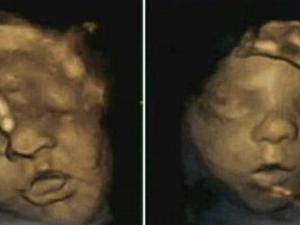

جنين

الجنين يتمرن على الابتسام استعداداً للقاء والديه